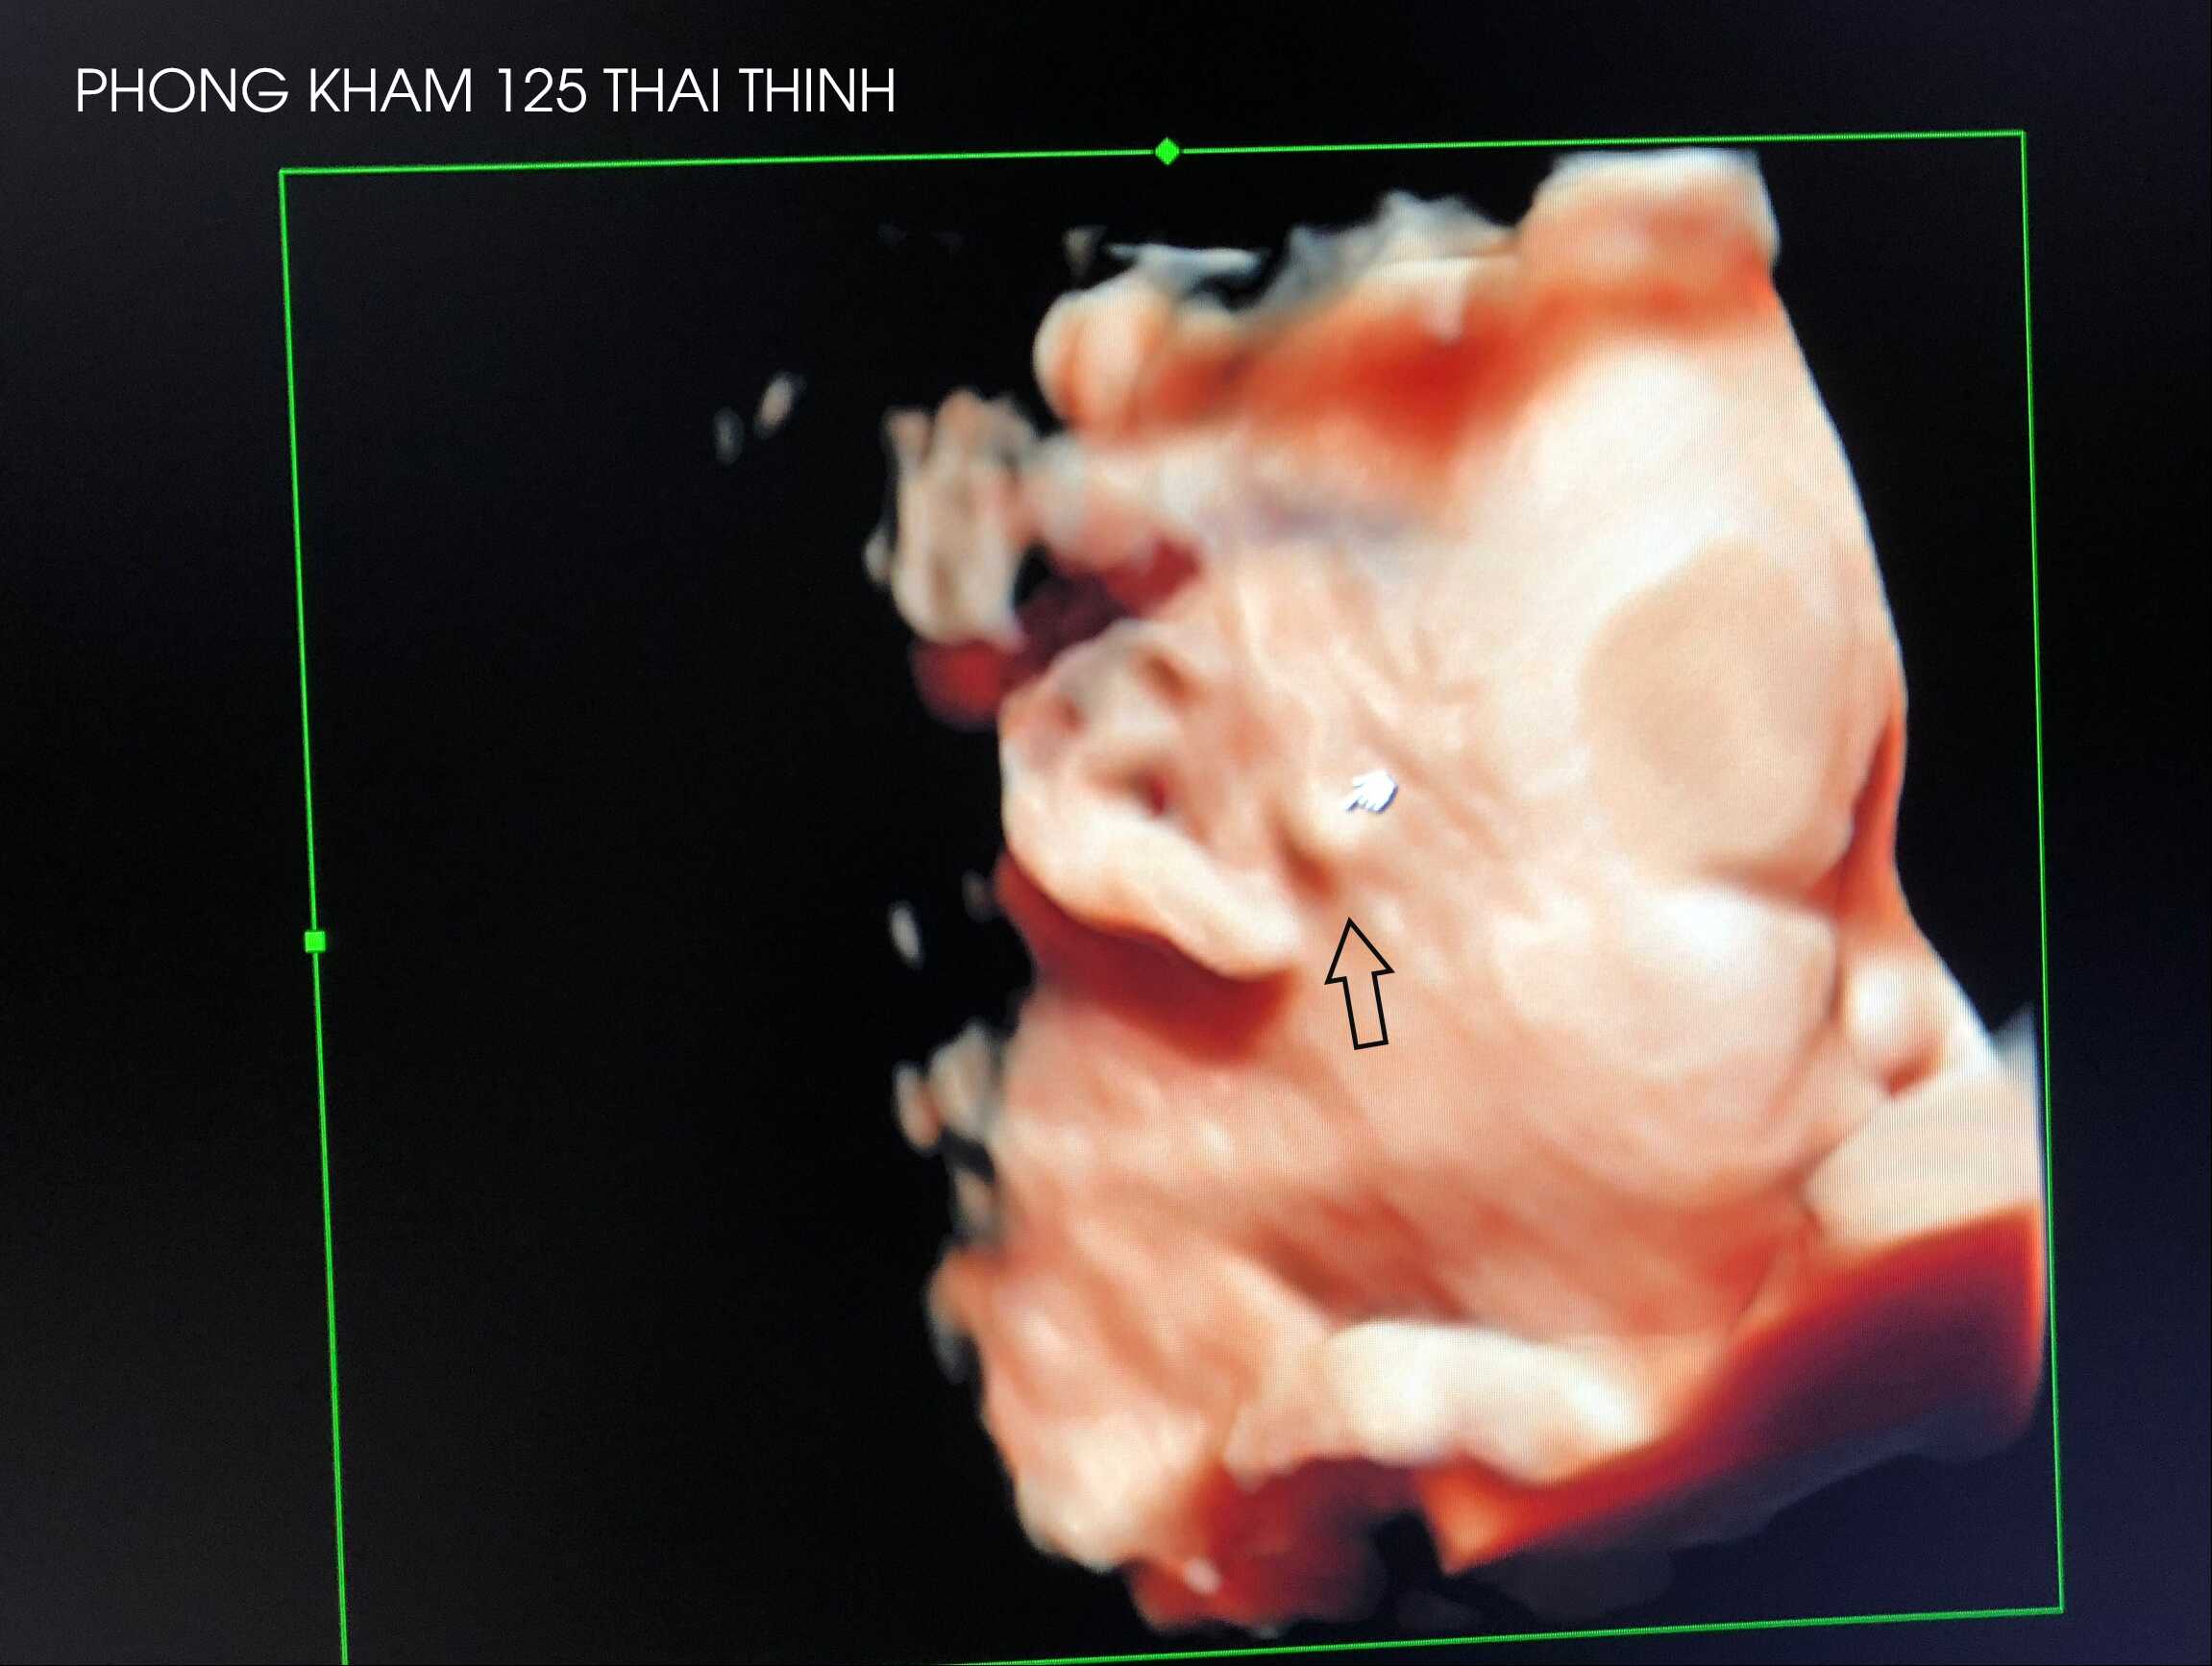

Hình ảnh thai nhi có thịt thừa trước tai được siêu âm tại Phòng khám 125 Thái Thịnh